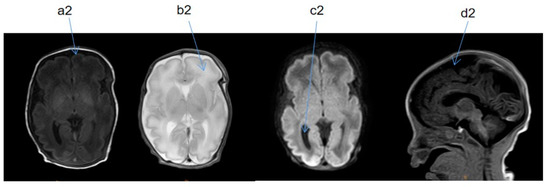

2.2. Supplementary Examination

| Cranial MRI abnormalities | + | + | + | + | + |